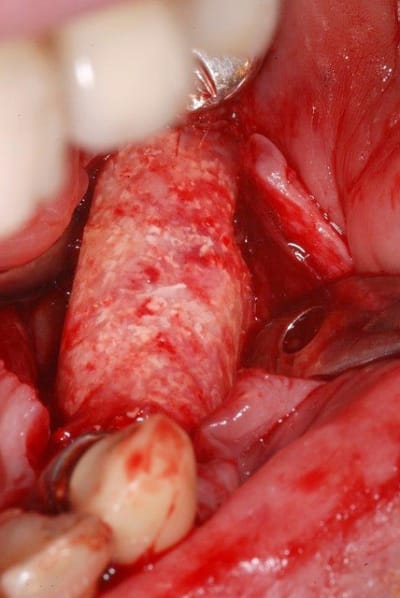

Growler, tu places quoi sous ta membrane ? biomat ? autogène ? mélange ?

Ta membrane armée, c'est la Citoplast Ti-250 ?